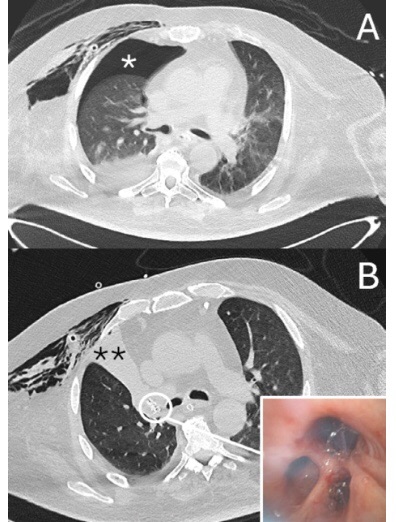

Le valvoline endobronchiali sono dei particolari device che sono utilizzate per il trattamento dell’enfisema polmonare o delle perdite aeree polmonari persistenti.

Un recente lavoro del nostro gruppo pubblicato sulla rivista internazionale Thoracic Cancer riporta l’utilizzo delle valvole endobronchiali, per la prima volta, in una serie consecutiva di pazienti sottoposti a ventilazione meccanica e con perfite aeree polmonari persistenti. In tutti i casi trattati io posizionamento delle valvole endobronchiali ha permesso la risoluzione delle perdite aeree e la rimozione del drenaggio toracico.